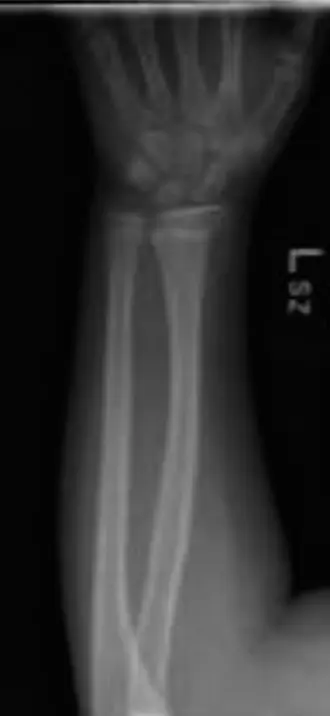

بعد التشخيص الدقيق، الذي غالبًا ما يتضمن الفحص السريري الدقيق وتصوير الأشعة السينية، وربما التصوير بالرنين المغناطيسي (MRI) أو الأشعة المقطعية (CT) في حالات معينة، سيقوم الأستاذ الدكتور محمد هطيف بوضع خطة علاجية مخصصة لطفلكم. تعتمد الخطة على عدة عوامل، منها: نوع الكسر أو الخلع، شدته، عمر الطفل، موضع صفيحة النمو، وحالة الأنسجة الرخوة المحيطة.